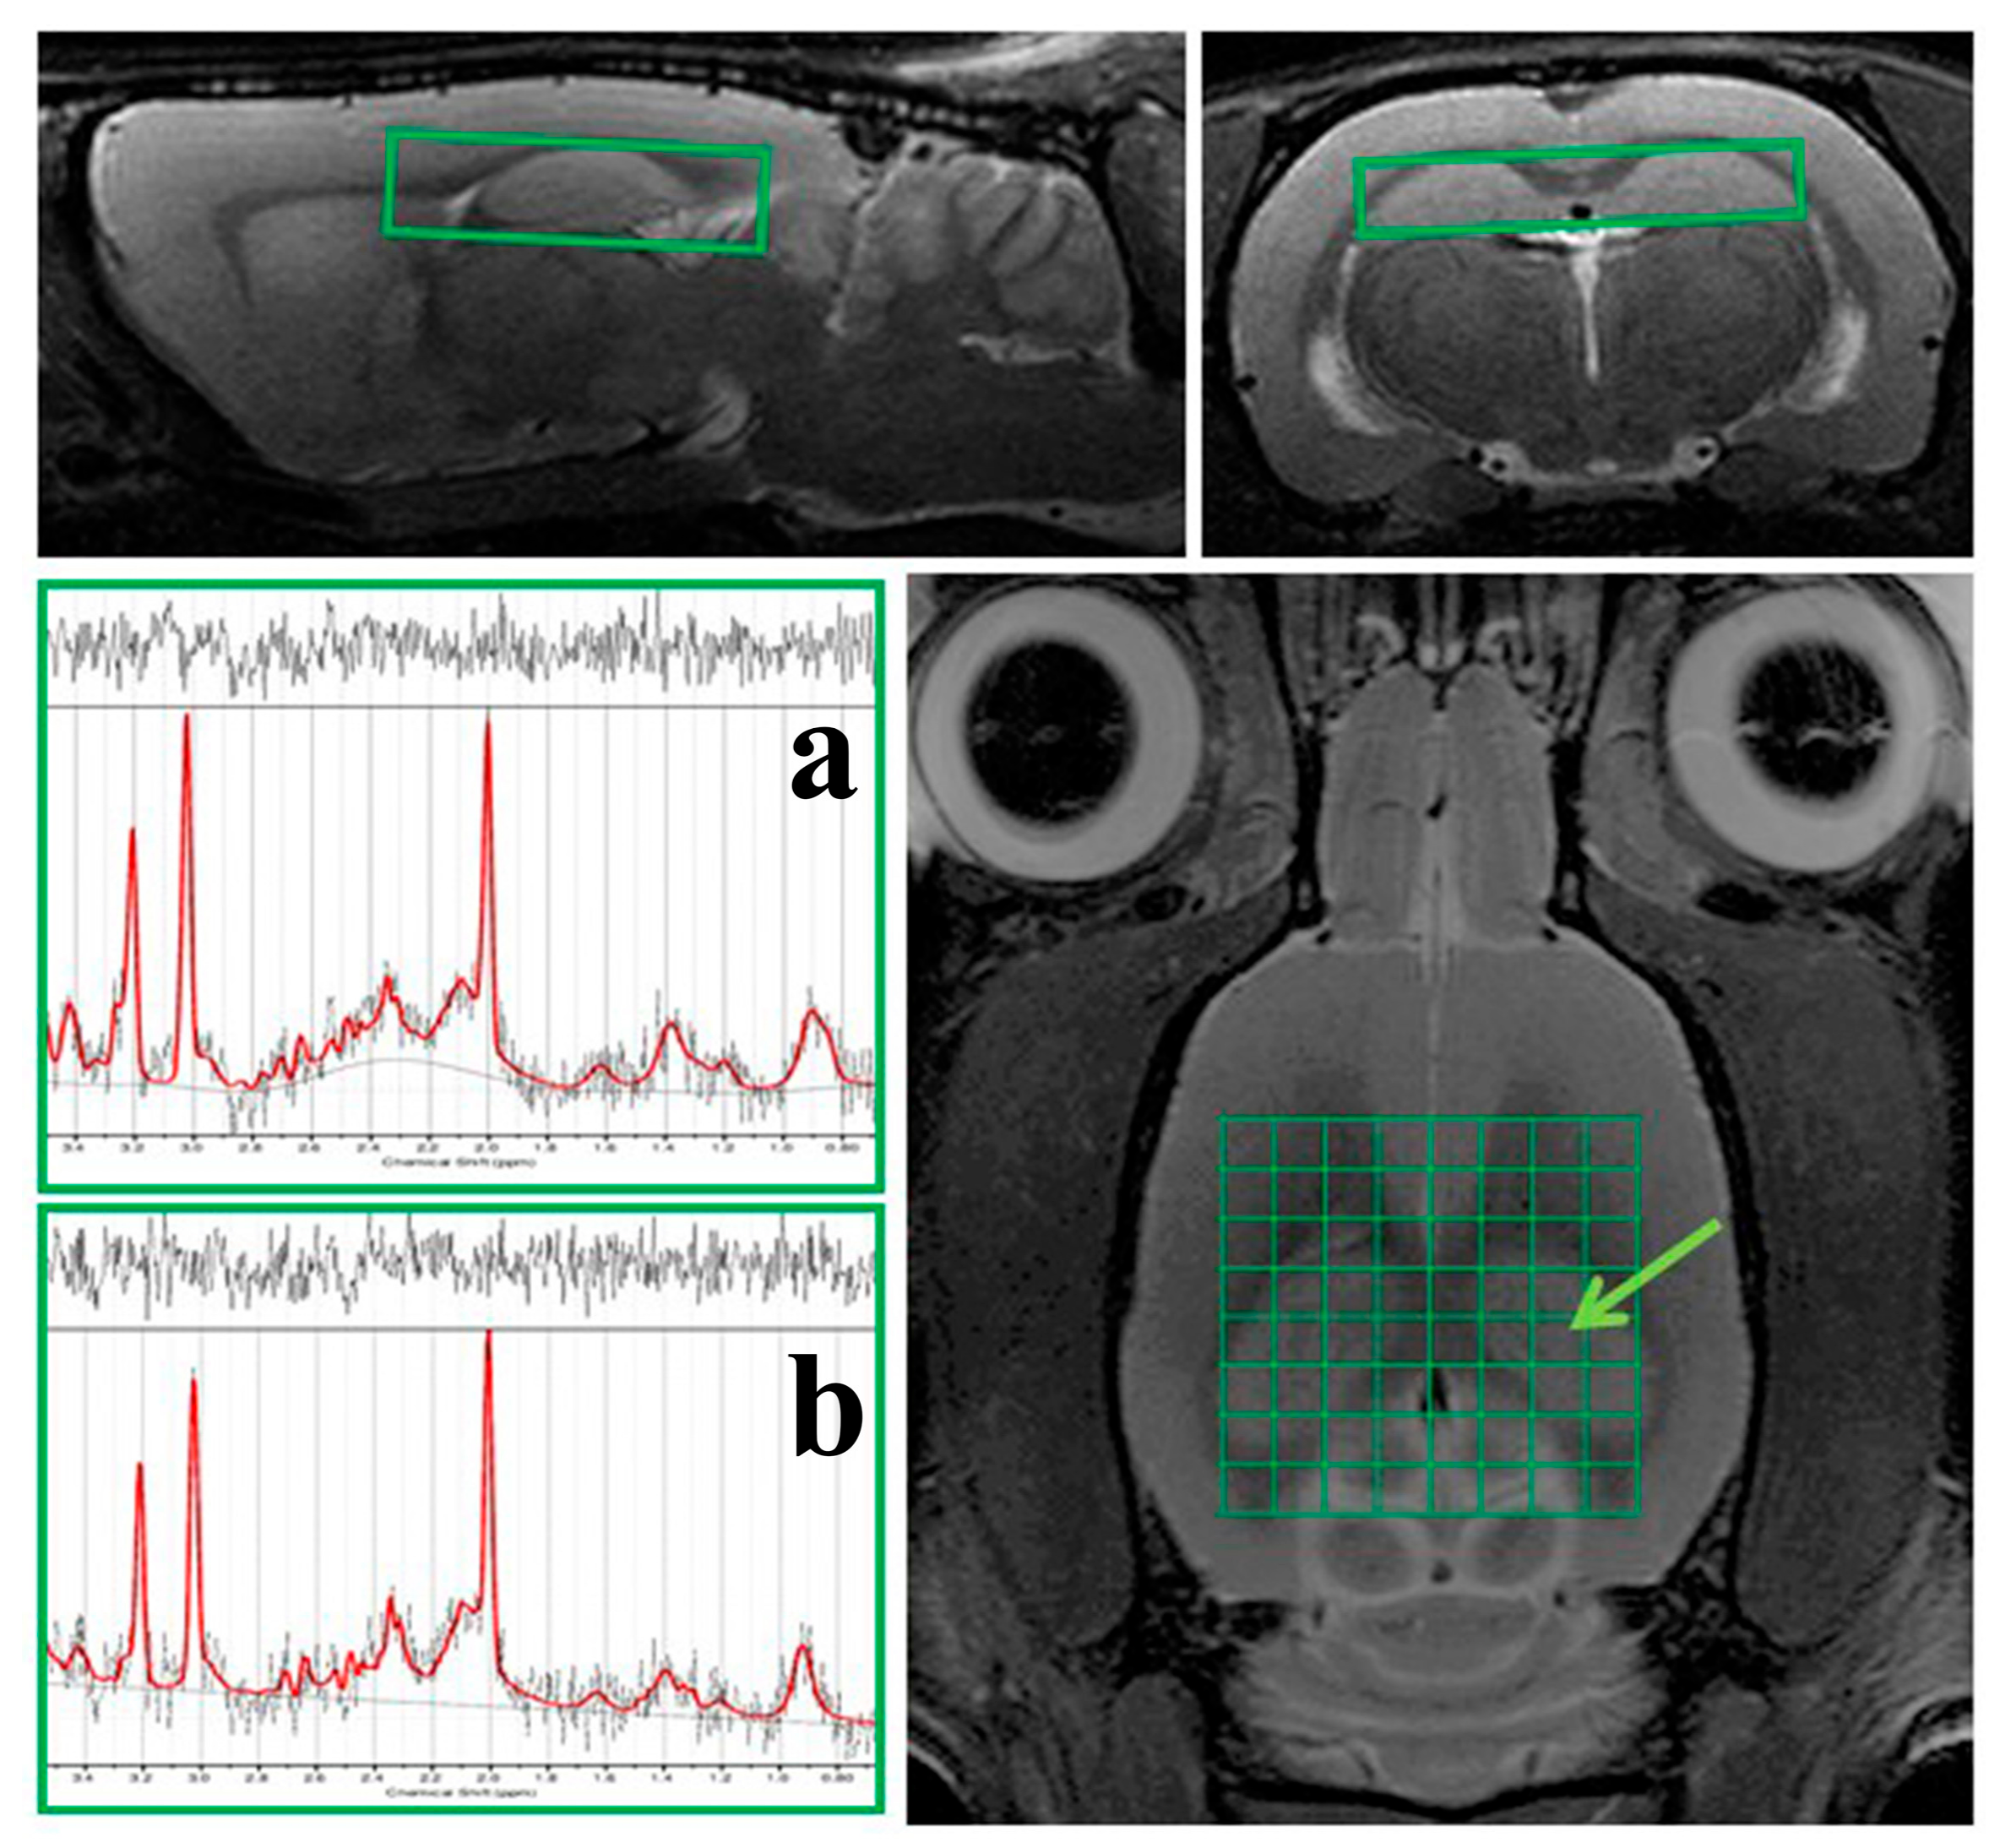

2.2. 1H MRS Analysis

MRI Volumetric Analysis